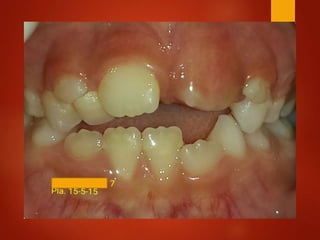

El documento es un registro médico odontológico que muestra las fechas de las visitas de un paciente al centro de salud El Raval, incluyendo exámenes y tratamientos realizados como la extracción de cálculos salivales en abril y mayo de 2012.